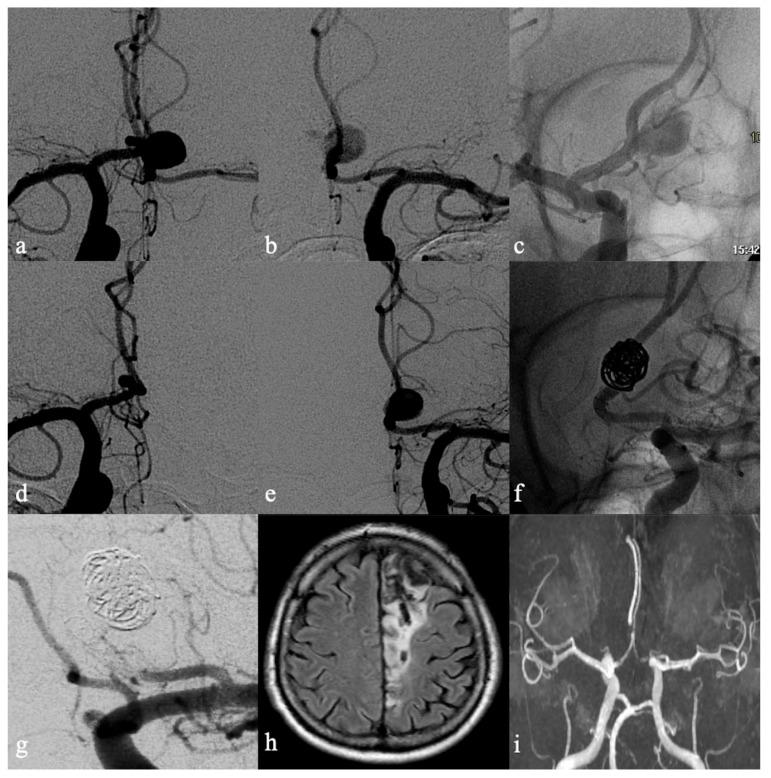

In this study, the authors evaluated the efficacy and the safety of flow diverter devices (FDD) in anterior communicating artery (ACoA) region aneurysms, focusing on anatomical factors that could affect the outcome, such as the location of the aneurysm along the ACoA (centered on ACoA or decentered on the A1-A2 junction) and the anatomy of the ACoA region.

33 patients (17 males; 16 females) with ACoA region aneurysms were treated with FDDs. 27 aneurysms were located at the A1-A2 junction (82%) while the remaining six aneurysms were centered on the ACoA. No mortality was recorded. The overall morbidity rate was 6% (2/33 procedures). Major complications occurred in 33% (2/6) of ACoA aneurysms and in the 0% of A1-A2 junction aneurysms. Mid-term and long-term neuroimaging follow-ups showed the occlusion of the aneurysm in 28/33 cases (85%). Complete occlusion rates were 93% in the A1-A2 junction aneurysms and 50% in ACoA aneurysms.

在本研究中,作者评估了血流导向装置(FDD)治疗前交通动脉(ACoA)区域动脉瘤的疗效和安全性,重点关注可能影响治疗结果的解剖学因素,如动脉瘤在ACoA上的位置(以ACoA为中心或偏离A1 - A2交界处)以及ACoA区域的解剖结构。

33例(17例男性;16例女性)ACoA区域动脉瘤患者接受了FDD治疗。27例动脉瘤位于A1 - A2交界处(82%),其余6例动脉瘤以ACoA为中心。无死亡病例记录。总体发病率为6%(33例手术中有2例)。主要并发症在6例ACoA动脉瘤中发生率为33%(2/6),在A1 - A2交界处动脉瘤中发生率为0%。中期和长期神经影像学随访显示,33例中有28例(85%)动脉瘤闭塞。A1 - A2交界处动脉瘤的完全闭塞率为93%,ACoA动脉瘤的完全闭塞率为50%。